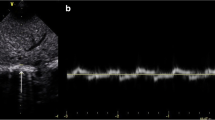

Using a recently published standardized technique [12, 19, 21,22,23,24,25], the right hemidiaphragm was assessed with the infant in a relaxed state facilitated by modified swaddling and occasionally pacifier administered by a second person. For DE measurements, the probe was placed subcostal between the anterior axillary and midclavicular line with a curvilinear probe using a standardized protocol for image acquisition. DE was measured as the difference in the position of the outer line of the diaphragm in M-mode at peak inspiration and expiration (Fig. 1a). DT was measured at the zone of apposition where thickening and shortening of the diaphragm could be appropriately evaluated. DT was obtained by placing the linear transducer at the 9th or 10th intercostal space near the mid-axillary line while the transducer was perpendicular to the chest wall [23, 24]. By B-mode, the diaphragm was identified as the hypo-echoic area (muscular layer) bordered by two echogenic lines of the diaphragmatic pleura (upper line) and peritoneum (lower line). Using M-mode tracing, the end of expiratory and inspiratory DT was calculated by determining the maximum perpendicular distance between the pleural and peritoneal layers, measuring only the distance of the hypoechoic area (Fig. 1b). To assess the efficiency of the diaphragm as a pressure generator, the DTF was determined [25]. DTF was calculated as the change in DTexp DTins using the following formula:

a, b Measurement of diaphragmatic excursion and thickness. a Measurement of diaphragmatic excursion using M-mode from a study patient, marked by the length of the orange arrows pointing up. b Measurement of diaphragmatic thickness at the end of inspiration and expiration using M-mode from a study patient, marked by the vertical distance (orange bidirectional arrows) between the 2 layers of diaphragm

For each diaphragm parameter (DTexp, DTins, DTF, and DE), the average from at least three respiratory cycles was reported to reduce the risk of over or underestimating the diaphragmatic measurements [26]. Standard neonatal LU views, three chest areas on each side (upper anterior, lower anterior and lateral) were obtained, and LUS using grading score (ranges from 0–18 points) were determined as previously described [27, 28].